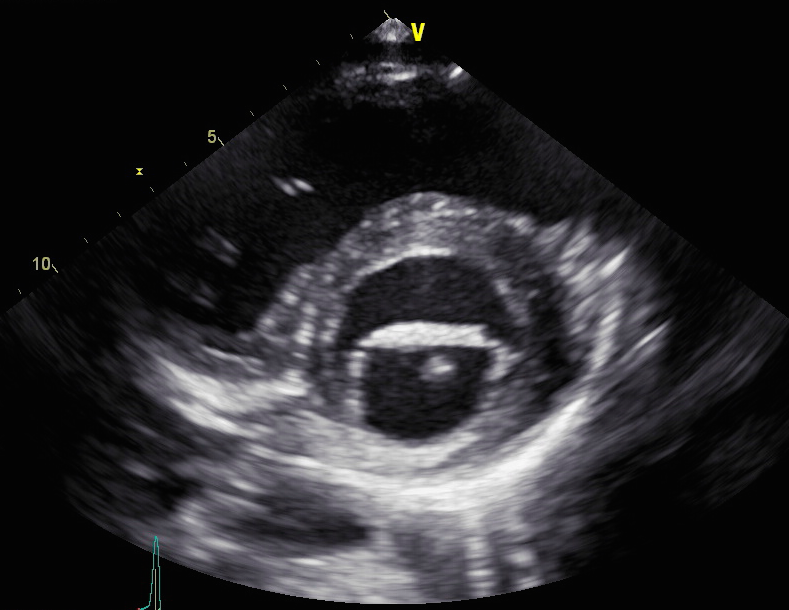

- Trans-esophageal echo [Fig 2,3] showed a mobile mass on the mitral valve. EF was 66% with normal LV function.